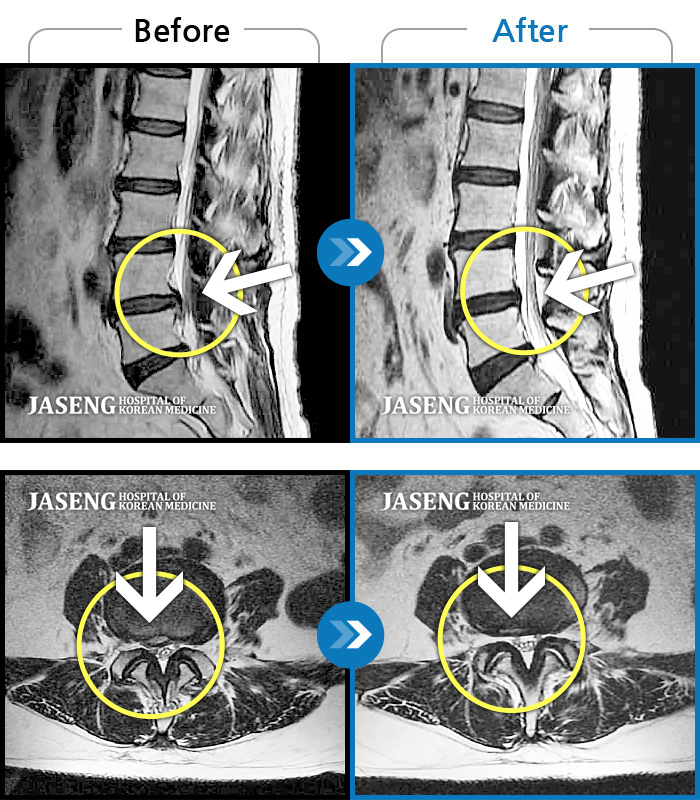

Xray 와 MRI 검사를 받았고

4번5번 척추사이 협착증과 유종이 원인이라고 하면서

한방 비수술치료로 2달동안 치료하면 나을 수가 있다고 말씀하셨고, 만약 한방치료로도 낫지 않으면 큰 대학병원 수술을 받아야 한다고 하면서 한방 비수술 치료를 권장해 주셔서, 박정우원장님의 치료를 받기 시작하였다.